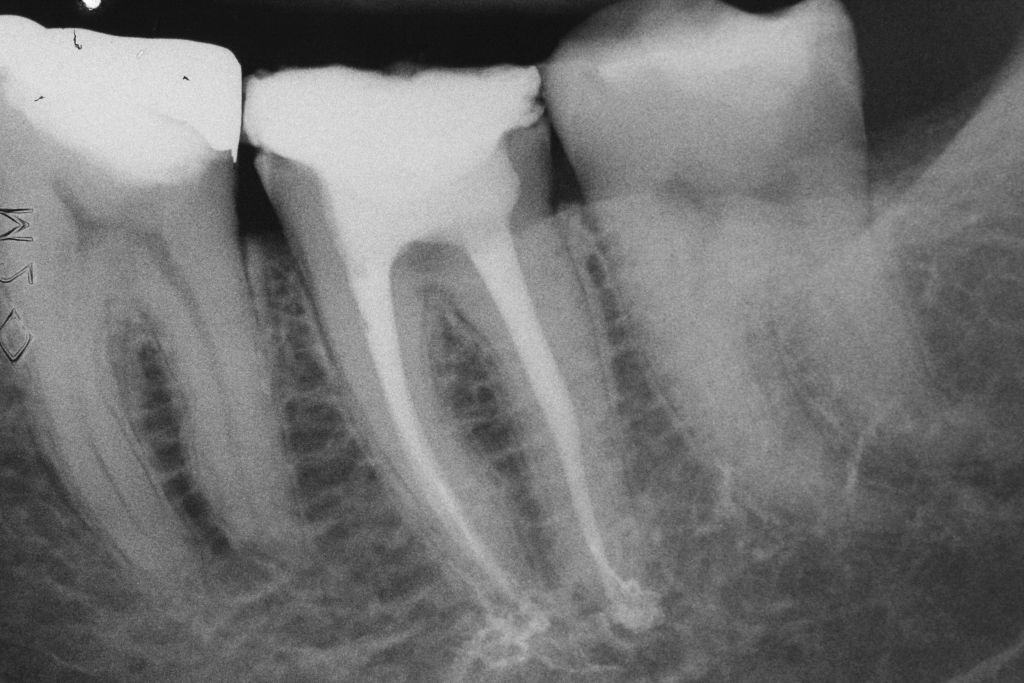

- Figura 7 – Radiografia final.

O cimento MTA Fillapex (Angelus) foi manipulado e levado ao interior dos canais por meio dos cones principais de guta percha. Os excessos dos cones foram cortados com a utilização de um sistema de transferência de calor (Touch’n Heat Sybron Endo), e compactados verticalmente a frio. A câmera pulpar foi selada com resina composta fotopolimerizável, e a paciente foi encaminhada à sua dentista para a realização da restauração definitiva do elemento dental.

Após 17 meses, a paciente compareceu para consulta de controle. Na radiografia foi possível observar sucesso endodôntico caracterizado por ausência de sinais e sintomas, dente em função fisiológica, normalidade do periápice e reabsorção do surplus de MTA Fillapex.